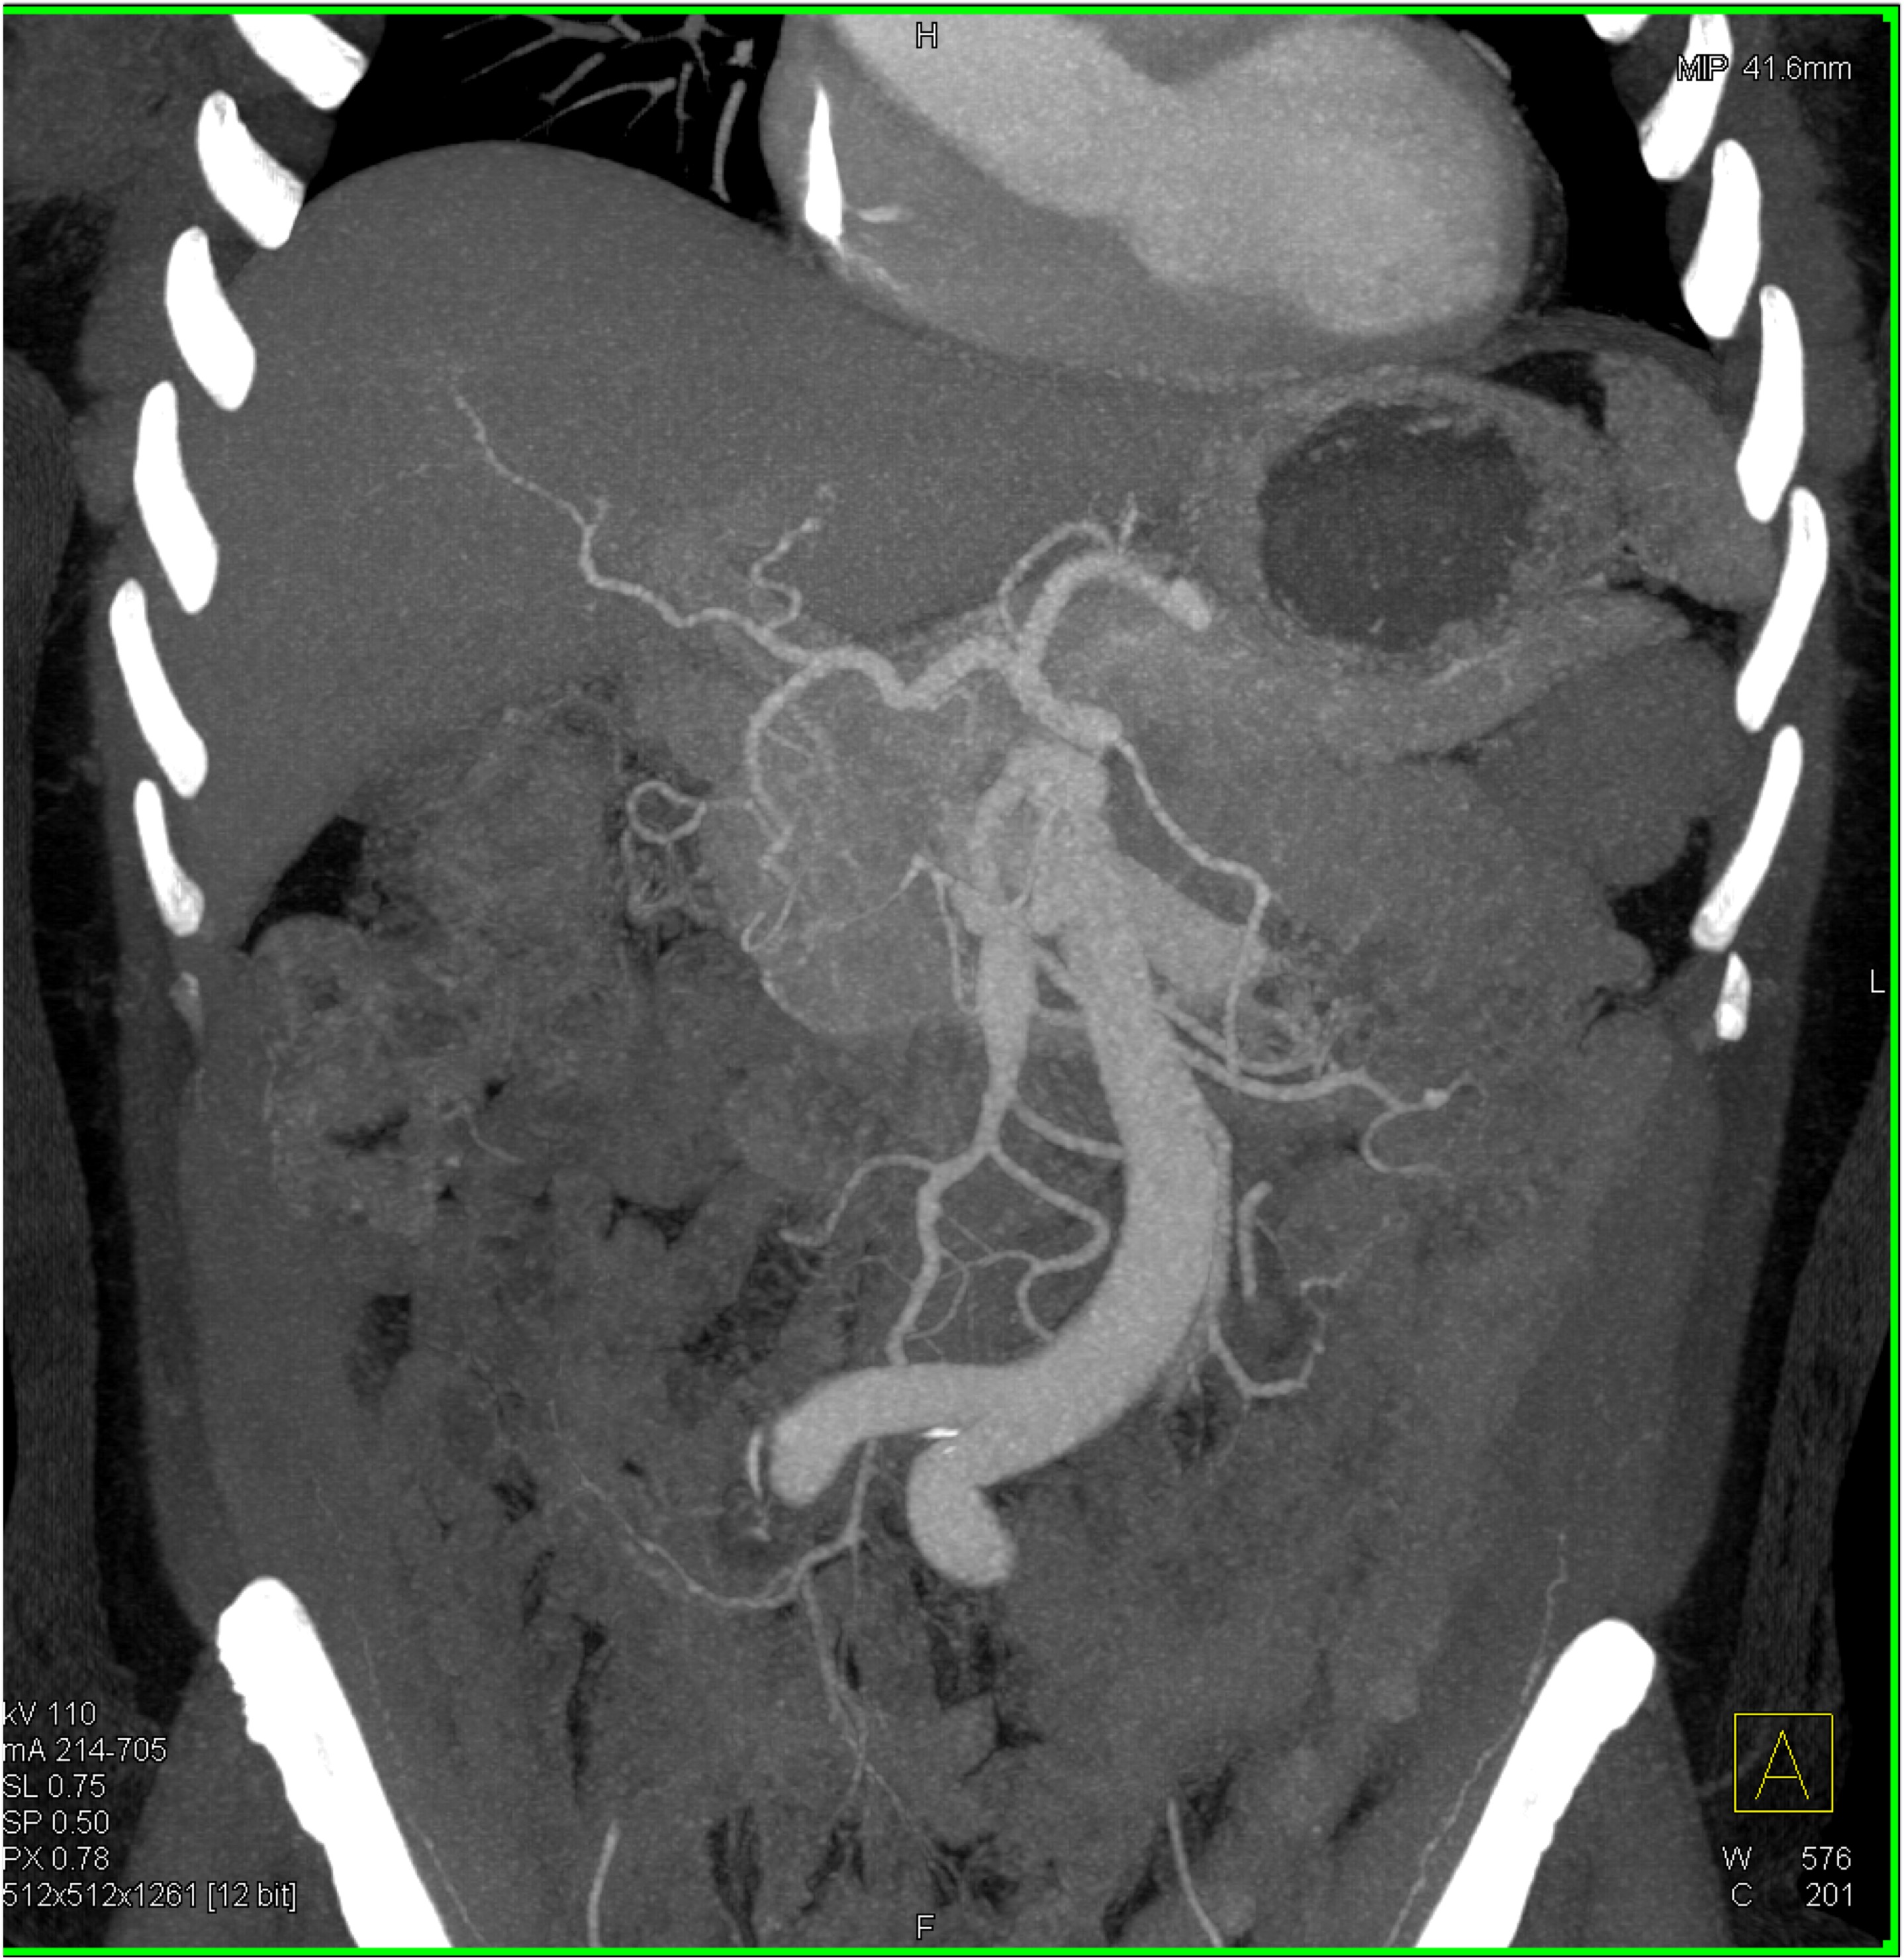

2) The differential diagnosis in this case includes?

FMD (fibromuscular dysplasia)

SAM (systemic arterial mediolysis)

Takayasu’s aortitis

all of the above